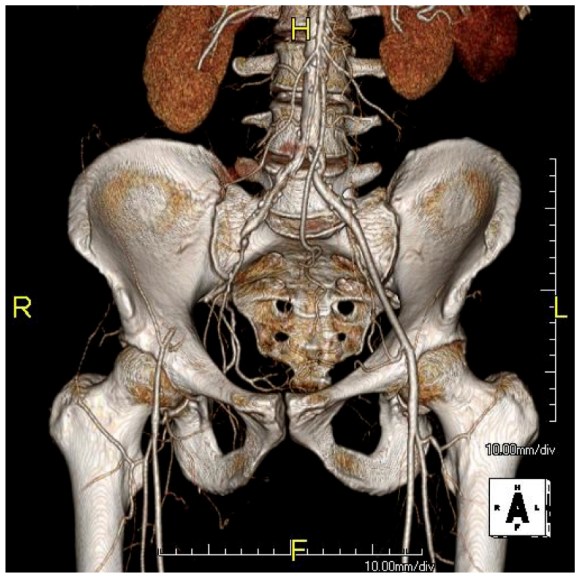

CTA showed that he had a CFA occlusion as well as SFA occlusion.

Because the common femoral plaque is contiguous with the external iliac plaque, it is often simpler to complete a remote endarterectomy over wire up to the external iliac origin than to try to get a satisfactory end point at the inguinal ligament -I do not like stenting across the ligament into the patch which is the usual bailout if the end point causes a stenosis. It is far simpler to apply a stent at the external iliac origin.

My intention was to endarterectomize the atherosclerotic plaque from the external iliac origin to popliteal artery via the groin incision marked in orange.

The plaque came out easily (first image, top).The proximal and distal end points required stents.